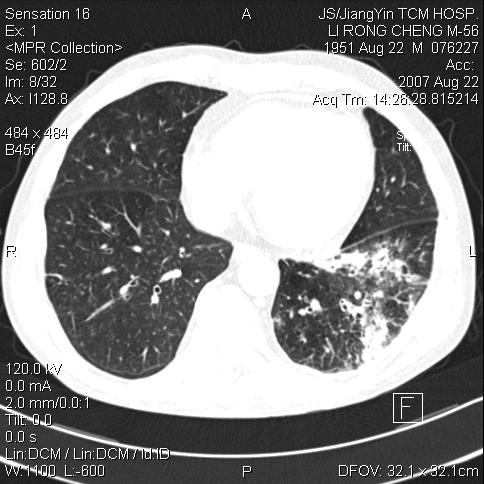

周围有支气管扩张影,伴片块状高密度影,有空洞和胸膜增厚,但是肋骨未见明显破坏,考虑炎性病变可能性大。

周围有支气管扩张影,伴片块状高密度影,有空洞和胸膜增厚,但是肋骨未见明显破坏,

考虑炎性病变可能性大。

左下肺团片状类软组织密度影,形态不规则,边缘欠规整,其内可见液化区及气体影,病灶内侧见引流支气管影,相邻胸膜反应性增厚。病灶周围肺野内见增粗支气管,壁厚,边缘模糊。考虑:支气管扩张并感染;肺脓肿。

左下肺炎性病变,有支气管扩张,考虑肺结核合并感染。